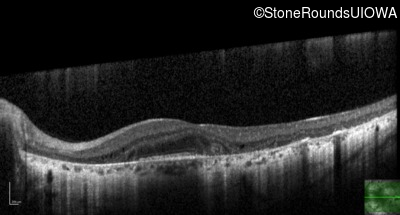

Age at visit: 35 years

This 35-year-old man has trouble in low light and when moving around in busy places. He first reported trouble seeing in low light at age 13. His maternal grandfather was similarly affected.